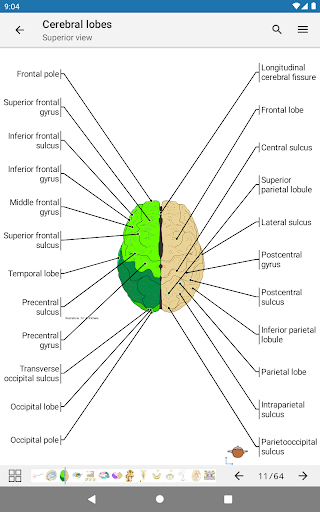

-The pins mode have a new behaviour allowing you to follow an anatomical structure much more easily

-You can now manually select the font size you prefer for your anatomical structures labels (in labels mode)

-Within the details view of an anatomical structure, a pin now points the related structure in all present images

Also tap directly on the image to navigate to the presented image in that module